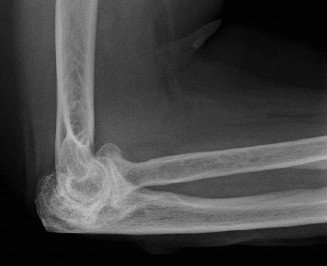

A 78-year-old female with a history of rheumatoid arthritis for the past 20 years presents to the office for …